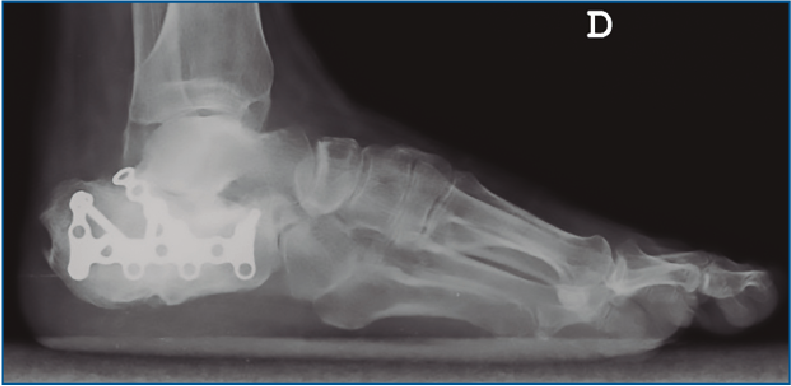

En aquellos a quienes se les planteó cirugía abierta se usó una vía de abordaje lateral extendida en “L” con una incisión ligeramente curva a nivel de la zona posteroinferior del calcáneo para evitar un ángulo recto y la necrosis apical del mismo. Se utilizó osteosíntesis con placas de tipo LCP (Figura 1) y, en casos clasificados como Sanders IV, artrodesis subtalar realizada con 2 tornillos canulados de 6,5 mm. El comienzo aproximado de la carga ha sido entre las 10 y las 12 semanas.

Figura 1. Reducción abierta fijación interna mediante placa tipo LCP. Vía de abordaje lateral en “L”.